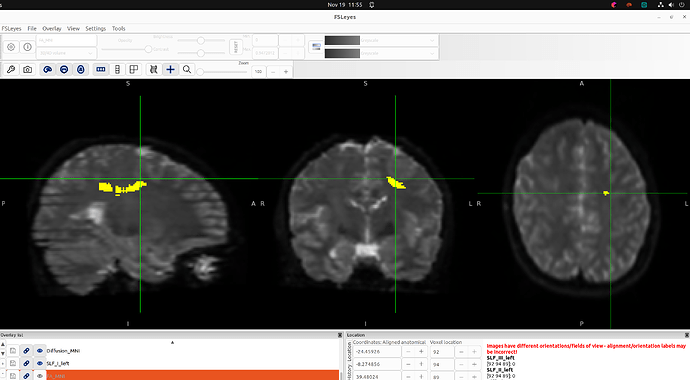

In both cases, my commands ran without errors, but when generating bundles with --nr_fibers, TractSeg reported that the tract masks were empty, and thus produced empty tractograms, even though the masks are visible when I open them in FSLeyes (see image).